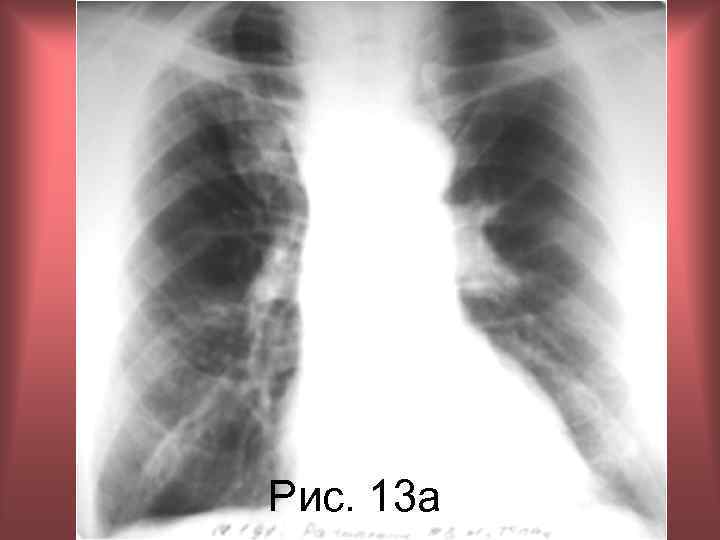

• Пациент Р. 61 г. Диагноз: Центральный перибронхиальный рак устьев первого и второго сегментарных бронхов верхней доли правого легкого. Клиника: два месяца пациент лечился по поводу пневмонии. Фибробронхоскопия: просвет сегментарного бронха второго сегмента верхней доли правого легкого обтурирован шаровидным образованием. Слизистая бронха визуально не изменена. На операции обнаружена опухоль устья первого сегмента правого легкого размерами 3, 0 х 4, 0(см), которая доходила до устья долевого бронха. • Рис. 13 а. Рентгенограмма органов грудной полости в прямой проекции. Прозрачность верхней доли правого легкого неравномерно снижена. Определяется неправильной формы затемнение в проекции второго сегмента верхней доли. Прозрачность легочного поля в области первого сегмента повышена в латеральном и снижена в медиальном отделе. Легочный рисунок повсеместно обогащен. Корни легких – расширены и структурны. Справа хорошо видна тень непарной вены. Реберно-диафрагмальный синус справа затемнен. Тень средостения деформирована за счет выбухания восходящей части дуги аорты. Н. С. Воротынцева, С. С. Гольев Рентгенопульмонология

Рис. 13 а Н. С. Воротынцева, С. С. Гольев Рентгенопульмонология